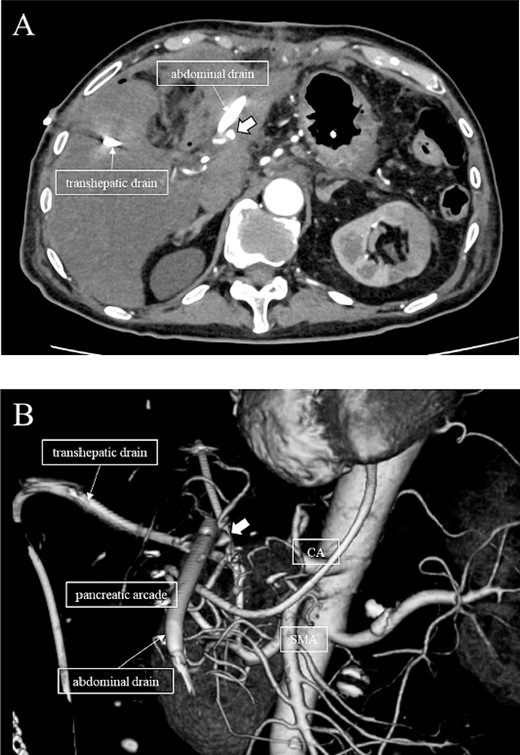

Subsequently, interventional radiology (IVR) was performed. However, because the inferior pancreaticoduodenal artery (IPDA) was very narrow, the microcatheter could not be followed, and hemostasis with IVR was difficult. Therefore, on POD 48, relaparotomy pseudoaneurysm repair was performed. The abdomen was opened through an inverted L-shaped incision, and adhesiolysis was performed, after which a pseudoaneurysm was revealed at the junction of the GDA and PHA. Four transfixing sutures with 3–0 prolene were used. After confirming that the liver blood flow was maintained, surgery was completed. However, bloody drainage from the drain was observed on POD 56. CeCT revealed a pseudoaneurysm (Fig. 3A and B). IVR was considered difficult because of the narrow blood vessels; therefore, the patient underwent a second laparotomy for hemostasis. A pseudoaneurysm was further observed at the junction between the GDA and PHA. In this operation, we used deeper and wider penetrating sutures than in the previous surgery to completely halt blood flow in the GDA. We confirmed that the blood flow to the liver was maintained; however, it was deemed weak. The patient had an uneventful postoperative course without bleeding, and CeCT performed on POD 61 confirmed the disappearance of the pseudoaneurysm. Although the blood flow in the PHA could not be confirmed, the right and left hepatic arteries were preserved (Fig. 4). On POD 76, CT revealed no liver abscesses or infarctions. The drain was removed on POD 78, and the patient was finally discharged on POD 107 without rebleeding or liver failure.

CT on postoperative Day 61. Although blood flow in the PHA could not be confirmed (arrow), the right and left hepatic arteries are preserved.

In this case, relaparotomy repair was performed for a pseudoaneurysm at the junction of the GDA and PHA. Preoperative CT showed no vascular variations. CeCT on POD 56 confirmed blood flow in the left and right hepatic arteries but not in the PHA. The CHA provides the main blood supply to the liver; however, the right and left accessory hepatic arteries and the inferior phrenic artery also play a role. Therefore, recent studies suggest that the CHA is not essential for parenchymal survival [10]. Collateral vessels are identified 4 h after vascular ligation and increase in size and number over the next 6 months [11]. Therefore, we speculate that collateral blood channels from the inferior phrenic artery and vessels of the lesser diaphragm had developed and hepatic blood flow was preserved in our case. In a search of the literature, we did not find any cases in which hemostasis was performed for a pseudoaneurysm at the junction of the GDA and PHA and hepatic blood flow was maintained by collateral blood vessels in a patient without a vascular anomaly, as in the present case. This suggests that IVR remains the best technique to achieve hemostasis for pseudoaneurysms, but, even when hemostasis by IVR is difficult, following some postoperative days, collateral vessels develop, and hepatic blood flow may be maintained even after relaparotomy pseudoaneurysm repair. Re-relaparotomy pseudoaneurysm repair after DP-CAR may be useful after some postoperative.